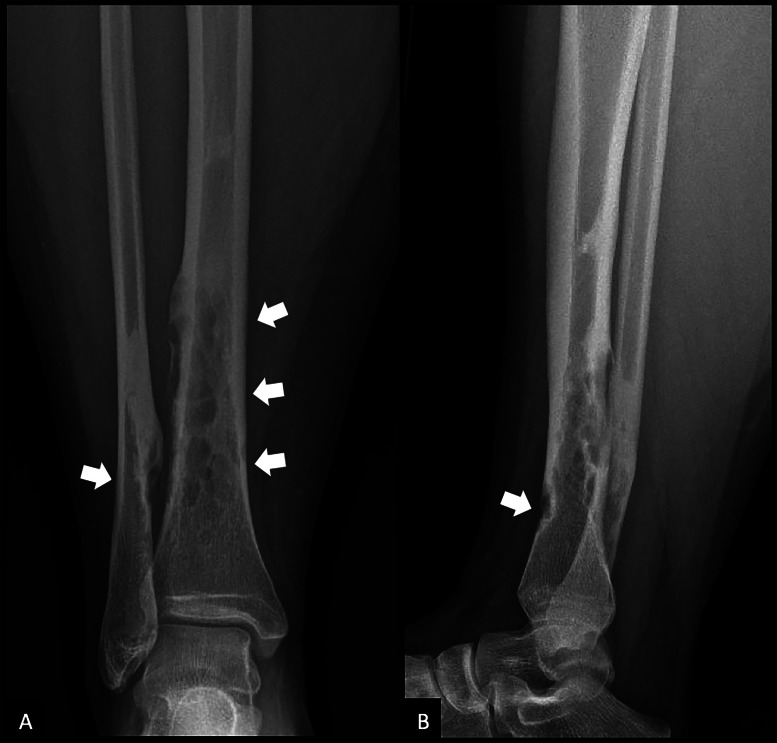

教学点:骨纤维结构不良(OFD)是一种罕见的良性纤维骨性病变,主要影响儿童和青少年的胫骨皮质;腓骨同时受累是罕见的,可能类似于更具侵袭性的肿瘤,如adamantinoma。

Teaching point: Osteofibrous dysplasia (OFD) is a rare benign fibro‑osseous lesion primarily affecting the tibial cortex in children and adolescents; simultaneous involvement of the fibula is exceptional and may mimic more aggressive tumors such as adamantinoma.